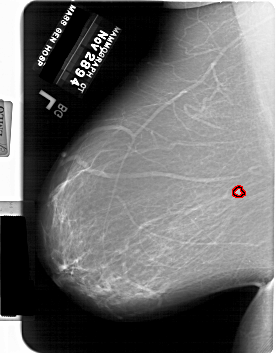

A_1769_1.LEFT_MLO

LEFT_MLO LINES 6706 PIXELS_PER_LINE 5236 BITS_PER_PIXEL 12 RESOLUTION 43.5 OVERLAY

FILE: A_1769_1.LEFT_MLO.OVERLAY

TOTAL_ABNORMALITIES 1

ABNORMALITY 1

LESION_TYPE MASS SHAPE LOBULATED MARGINS ILL_DEFINED

ASSESSMENT 4

SUBTLETY 4

PATHOLOGY BENIGN

TOTAL_OUTLINES 1

BOUNDARY